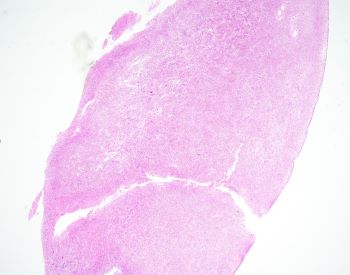

Sections show large polypoid, densely cellular fragments of endometrial stroma composed of bland cells that are small and uniform, resembling proliferative-type endometrial stroma. Admixed within this stroma are sex cord-like elements, arranged in cords, trabeculae, and retiform patterns. Endometrial stromal nodules are rare tumors. They can display a number of different histologic variants, including sex cord-like elements (as in this case), smooth muscle, endometrioid glandular elements, and myxoid/fibroblastic. A characteristic network of arterioles around which neoplastic cells often whorl is distinctive as well. A diagnosis of an endometrial stromal nodule can only be definitively made after ensuring there is no myometrial or lymphovascular invasion, and often this requires a resection rather than just a biopsy. This brings up an important differential: low-grade endometrial stromal sarcoma, as invasion renders the diagnosis of sarcoma. So, it is best to defer a definitive diagnosis to a resection specimen. Both nodules and sarcomas have similar histologic features, including sex cord-like elements. Both are also characterized by a t(7;17)(p15;q21) translocation resulting in JAZF1-SUZ12 fusion (there are others, but this is the most common).

Uterine tumor resembling ovarian sex cord tumor is also in consideration. However, the presence of endometrial stroma excludes this diagnosis. An endometrial polyp could come under the differential here as well, given the large polypoid fragments and larger, thick-walled blood vessels. The important diagnostic feature lacking in this case for a polyp are branched or cystically dilated endometrial glands within an altered, fibrotic stroma. The presence of sex cord-like elements really excludes the possibility of a cellular leiomyoma, but stromal tumors and uterine smooth muscle tumors (ie leiomyomas) can have overlap. Features favoring a cellular leiomyoma include prominent thick-walled blood vessels and cleft-like spaces.